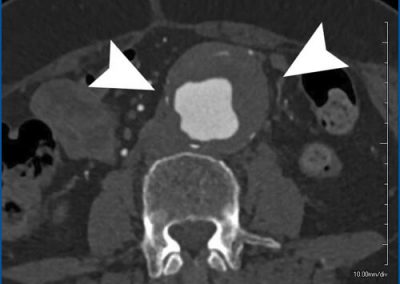

All images, protocols, and outcomes are courtesy of Dr. Richard Hallett, Banner University Medical Center – Phoenix, Phoenix, AZ.